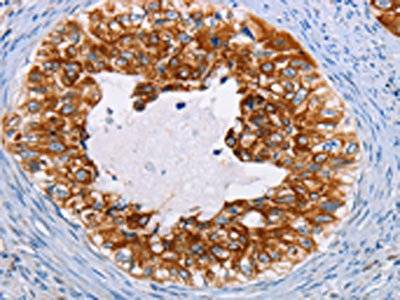

The image on the left is immunohistochemistry of paraffin-embedded Human cervical cancer tissue using CSB-PA297945(KRT13 Antibody) at dilution 1/35, on the right is treated with fusion protein. (Original magnification: ×200)